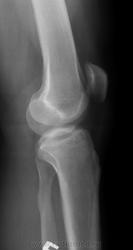

Пол пациента: Мужской пол Тип патологии: Травма Область исследования: Скелетно-мышечная система Методы исследования: Rg Травма, 50 лет, падение на колено, хирург искал перелом надколенника. Что за очаги оссификации? https://radiomed.ru/sites/default/files/styles/case_slider_image/public/user/17212/3.jpg?itok=ZOARUHOu https://radiomed.ru/sites/default/files/styles/case_slider_image/public/user/17212/4.2.jpg?itok=FzC0cneJ https://radiomed.ru/sites/default/files/styles/case_slider_image/public/user/17212/4.jpg?itok=jE1z60Rz ID:28343 Thu, 02/05/2013 - 13:17 #1 И.Бондаренко Offline Last seen: 13 hours 12 min ago Joined: 13.09.2011 - 22:55 Posts: 9206 Возможно обычная остеопойкилия. Thu, 02/05/2013 - 22:30 #2 Almo Offline Last seen: 18 hours 5 min ago Joined: 28.09.2008 - 18:50 Posts: 8259 +1.

Возможно обычная остеопойкилия.